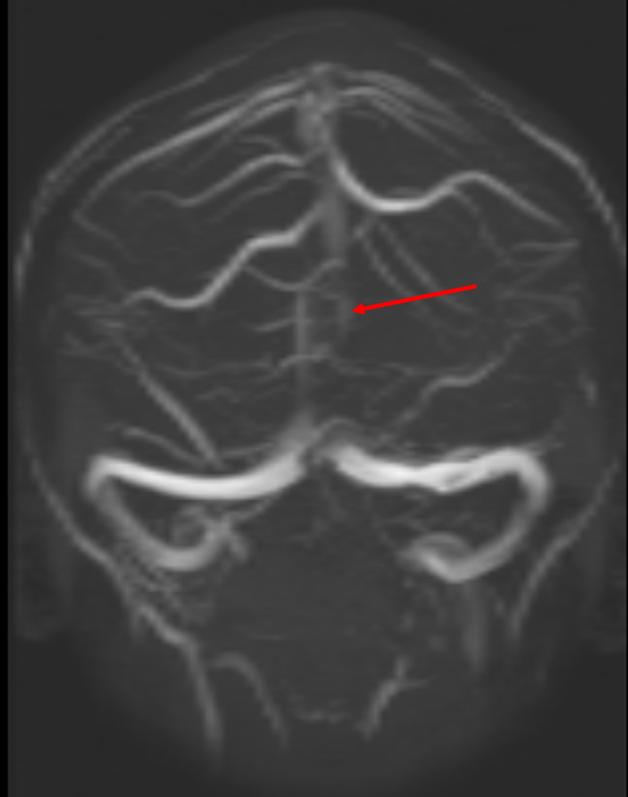

Cerebral vein thrombosis

MRI with sagittal vein cerebral vein thrombosis (notice lack of filling)